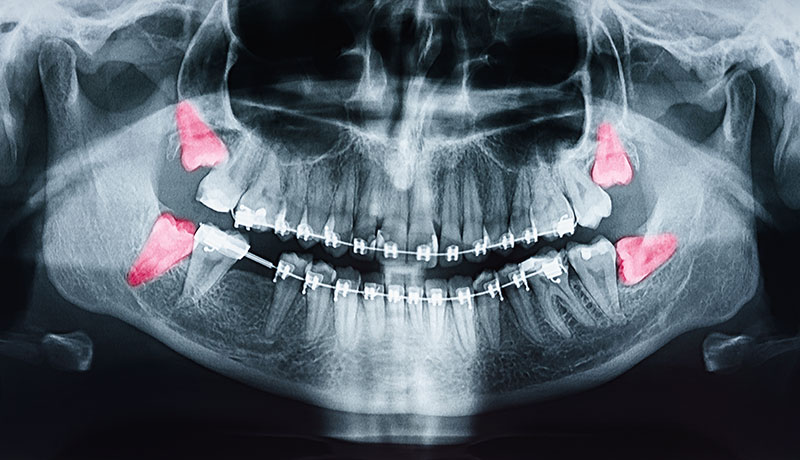

口腔外科

親知らずの抜歯をはじめ、顎や粘膜に関する外科的処置を行います。

痛みや腫れ、歯並びへの影響を最小限に抑えるため、的確な診査と抜歯の計画を立てております。抜歯の必要性は、親知らずの生え方を診査し総合的に判断致します。

矯正歯科

矯正歯科は、歯や顎の骨の位置を整え、歯並びと噛み合わせを改善する治療です。

見た目の美しさだけでなく、噛む機能や発音の改善、虫歯、歯周病の予防効果もあります。正しい咬合バランスを整えることで、長期的な口腔健康の維持を目指します。